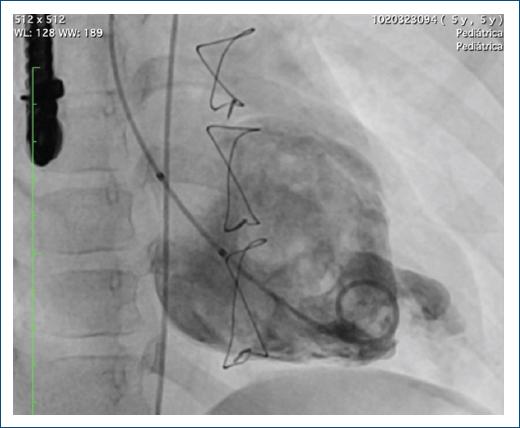

Se llevó de nuevo el caso a junta médico-quirúrgica, donde se consideró el cierre del defecto por vía endovascular (Fig. 5). Para ello, se avanzó una guía hidrófila dentro del divertículo y sobre esta se pasó un catéter non taper hasta el cuerpo del divertículo. Se realizó angiografía en proyecciones oblicua derecha y lateral, observando el gran divertículo con un boca proximal tipo túnel.

Figura 5 Ventriculografía izquierda con ventrículo de morfología izquierda, posterior, con segmento apical con divertículo gigante, con trabéculas en su interior, con fuga residual del parche de pericardio, visualizada previamente en la ecocardiografía.

Se pasó un introductor Flexor 6 Fr hasta el ventrículo izquierdo, luego se avanzó al catéter non taper distal en el divertículo y se pasó un guía de soporte Amplatz 0.035, sobre la cual se pasó un catéter guía JR 6 Fr. Se avanzó un AVP II de 10 mm, liberando el extremo distal y el tambor central en la cavidad del divertículo y en la boca distal, y por último se liberó el disco proximal (Fig. 7). Se realizó una maniobra de Minessotta wiggle para evaluar la estabilidad del dispositivo, que permaneció estable, y finalmente se liberó (Fig. 8). La angiografía de control mostró el dispositivo en posición con oclusión del divertículo (Fig. 9).

El procedimiento se realizó con ecocardiografía transesofágica y transtorácica en forma simultánea, demostrando en la imagen final la desaparición del flujo dentro del divertículo. Se observó la bolsa pericárdica apical izquierda sin cortocircuito residual. En la punta del ventrículo izquierdo se observó una bolsa pericárdica residual ocluida completamente por el dispositivo Amplatzer Vascular Plug II de 10 mm, con función ventricular sistólica conservada y excursión sistólica del anillo tricúspide de 21 mm (Fig. 10).